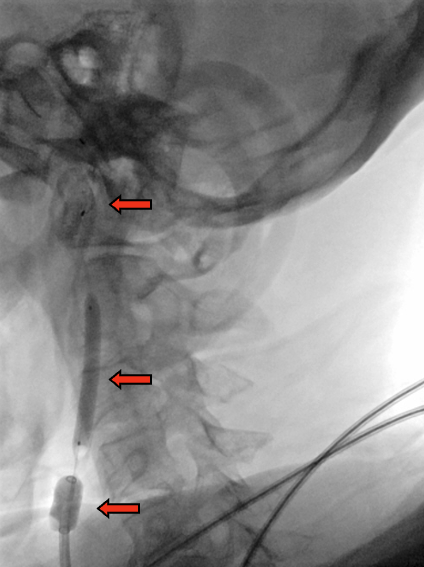

路图引导下,BGC置于颈总动脉,病变近端充盈球囊

球囊充盈后,手推造影,造影剂滞留能进一步明确狭窄病变特征。开放阀门(stopcock),可见造影剂回流,提示反向血流建立

路图引导下,导丝通过狭窄

远端保护伞到位

图1. 当BGC工作时,颈总动脉、颈内动脉、颈外动脉、Willis环中颈内动脉的血流方向示意图。(注:箭头代表血流方向)